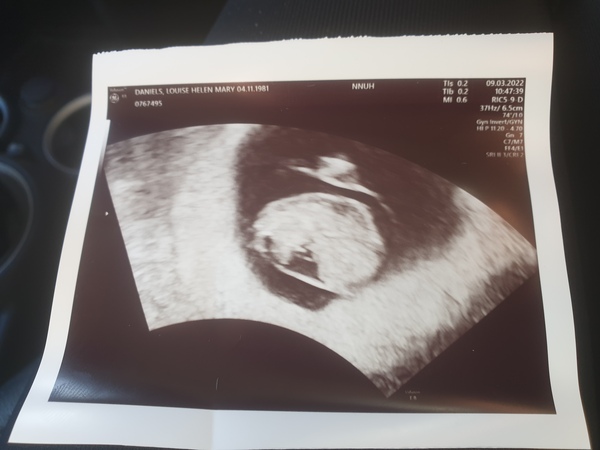

NorfolkBird · 09/03/2022 11:48

I'm 9 wks 2 days thought I was 3 days. Baby has a heartbeat & it all looks good so far so happy!!!

Due October 2022 thread #2 ... the first trimester continues!

@NorfolkBird I'm so happy to see this! You're 1 day ahead of me, huge congratulations to you